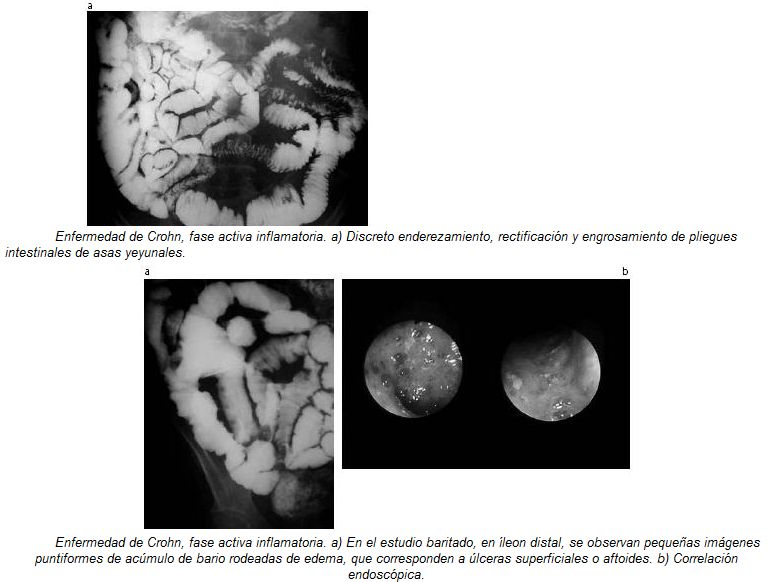

Resonancia Magnética Enfermedad Inflamatoria Intestinal, , , , , , , 0, EPOS™ - S-0978, epos.myesr.org, 1224 x 1863, jpeg, WebLa enfermedad inflamatoria intestinal (EII) comprende principalmente la colitis ulcerosa crónica idiopática (CUCI) o colitis ulcerosa, la enfermedad de Crohn (EC) y la colitis. WebLa resonancia magnética (RM) es una técnica de imagen que no utiliza radiación ionizante y permite identificar cambios inflamatorios en el intestino delgado y el colon, así como., 20, resonancia-magnetica-enfermedad-inflamatoria-intestinal, Novedades y Muebles WebLa enfermedad inflamatoria intestinal (EII) comprende principalmente la colitis ulcerosa crónica idiopática (CUCI) o colitis ulcerosa, la enfermedad de Crohn (EC) y la colitis. WebLa resonancia magnética (RM) es una técnica de imagen que no utiliza radiación ionizante y permite identificar cambios inflamatorios en el intestino delgado y el colon, así como.

WebEl objetivo de investigación de la Unidad de Enfermedad Inflamatoria Intestinal del Hospital Clínic de Barcelona es desarrollar una investigación traslacional que resulte en una. WebEl objetivo de la ENTERO – RM, también llamada RESONANCIA DE INTESTINO es visualizar las paredes del intestino, y poder determinar si presenta alguna. WebResonancia Magnética en el diagnóstico de las enfermedades intestinales. La Resonancia de Intestino también se llama Entero Resonancia y es una prueba. WebLa investigación de la EII se realiza a través del grupo de Enfermedad Inflamatoria Intestinal del IDIBAPS, dentro del Área de Hígado, Sistema digestivo y metabolismo. Las. WebEl objetivo del tratamiento de la enfermedad intestinal inflamatoria es reducir la inflamación que desencadena los signos y síntomas. En el mejor de los casos, podría. WebLos tipos de enfermedad inflamatoria intestinal incluyen: Colitis ulcerosa : esta condición causa una inflamación duradera y úlceras en el revestimiento del.